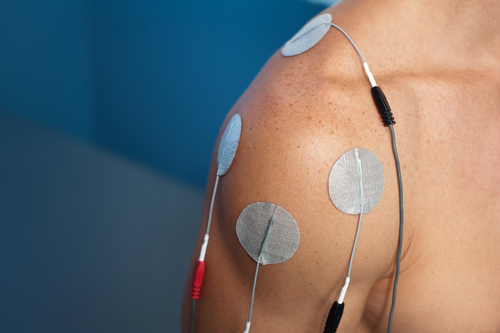

神经肌肉电刺激治疗上肢瘫痪

使用神经肌肉电刺激治疗上肢瘫痪作者:Mikayla Murphy Martin, R.、Johnston, K. 和 Sadowsky, C. (2012)。神经肌肉电刺激辅助抓握...